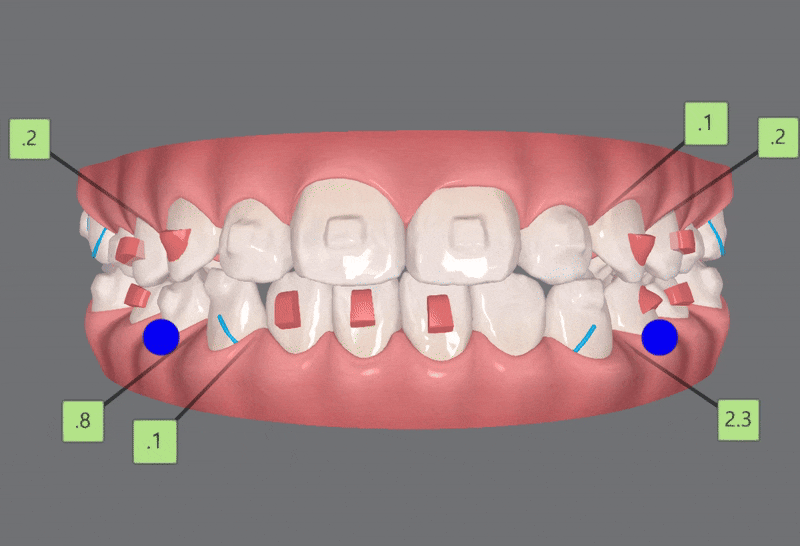

2nd ClinCheck(18개)

두번째 클린체크는

첫번째 클린체크에 추가적으로 어태치먼트를 부착하여 18개의 장치로

치아배열을 개선시켜 주었습니다.

송파소아인비절라인 전문

송파어린이인비절라인 전문

유펜바른치과에서는

이전의 클린체크와는 어태치먼트의 모양과 위치가

달라져

이전의 클린체크를 보완해 교정치료의 완성도를 높여 줍니다.

어태치먼트란?

치아의 회전이나, 이동, 높이, 각도 등을 조절할 수 있는 장치로

레진을 치아에 부착해서

치아의 이동을 원하는 위치로 올바르게 배열시켜 주는

인비절라인에서 없어서는 안 될 필수!! 요소입니다.